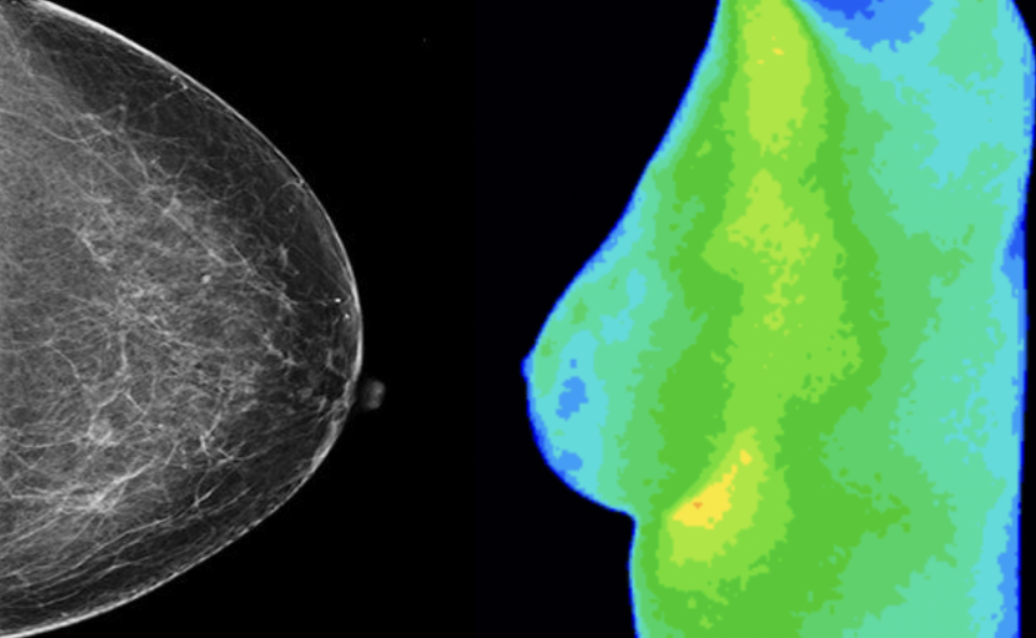

A mammogram is an x-ray of the breast used to detect structures. The structures typically take years to form to where they can be seen on a mammogram.

Thermography is a test that uses infrared heat to detect physiological and functional changes. Because thermography sees inflammation, it can be used to identify areas that may be at risk for disease years before it shows up as a structure on a mammogram – making it a great way to be preventative and proactive about your breast health.

Thermography can help create a more complete picture of breast health when done in conjunction with mammography. We do not believe thermography is meant to replace a mammogram but is a non-invasive addition to a yearly breast health check routine.